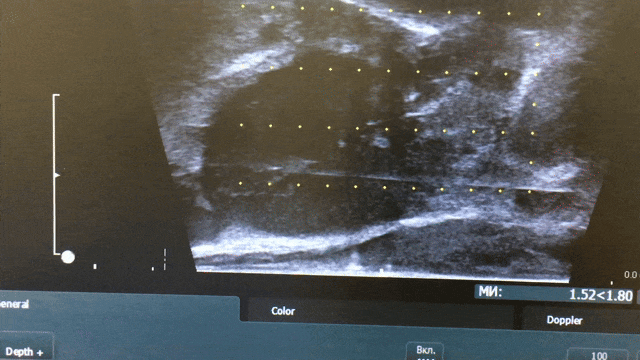

За даними мультипараметричної МРТ було виявлено новоутворення розмірами 12×13×8 мм у лівій частці передміхурової залози, в ділянці верхівки.

За результатами патогістологічного дослідження після 12-точкової біопсії встановлено діагноз: аденокарцинома передміхурової залози, 6 балів за Глісоном (3+3), G1, із ураженням приблизно 25% тканини у трьох біоптатах.

Пацієнту була виконана біполярна фокальна абляція пухлини простати.

Протягом двох років спостереження рівень ПСА знизився з 9 нг/мл до 1,1 нг/мл, що є нормальним показником для пацієнтів цього віку.

За даними контрольного МРТ, проведеного через рік після фокальної терапії, патологічних вогнищ не виявлено.

Повторна біопсія підтвердила наявність чітко окресленої ділянки склерозу в зоні проведеного лікування без ознак злоякісного процесу.